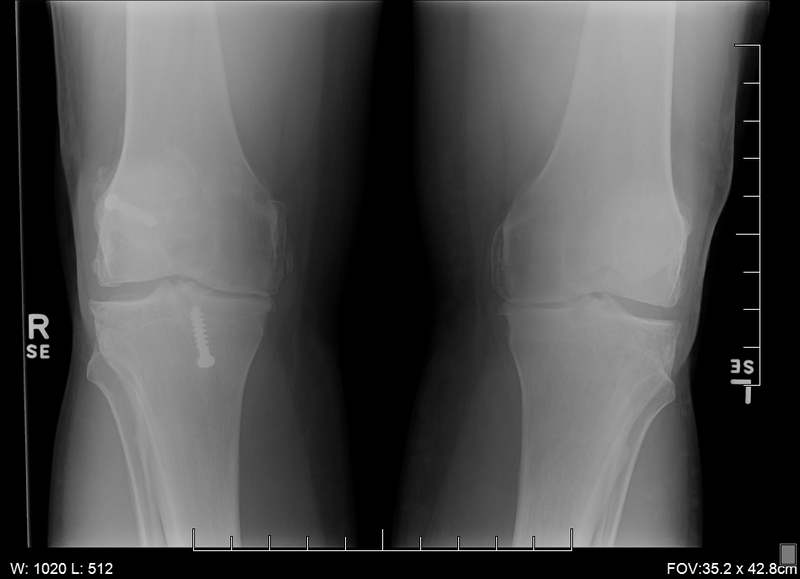

Those x-rays look like mine did prior to surgery :-(. I started to really feel my OA as I hit 49. Tried glucosamine supplements, hyaluronic acid injections and worked with 2 different PTs to see if muscle strengthening could help alleviate pain and inflammation.....none of these really did anything. I could take 4 Advil at a time with pretty much no effect. In the end, if you have bone on bone, it's just up to you to decide when your quality of life has become an issue. I hesitated on TKR for quite a while due to being younger and worries about how long the implants will last. Couldn't stand in one place for more than 10 minutes, couldn't really walk more than a half mile without pain becoming an issue. Still did plenty of diving and kept in shape via lots of lap swimming...but in the end, I was missing out on parts of life....and why not get that function back now when I can really enjoy it?

Today I am at 3 weeks and 1 day following TKR #1. I had my post-surgery check-up, stitch removal and x-rays last week...amazing to compare the x-rays between new knee and yet-to-be-replaced knee = TKR knee beautifully aligned, perfect space between femur and tibia.....vs. my other knee which looks a lot like your x-rays above....bow-legged and bone-on-bone. There have been times during this process where I groan since this it is a long road and this is just the first of 2.....but seeing those x-rays (and how much better I feel this week) actually made me more enthusiastic about following through with both.

Pre-surgery x-rays

View attachment 397127